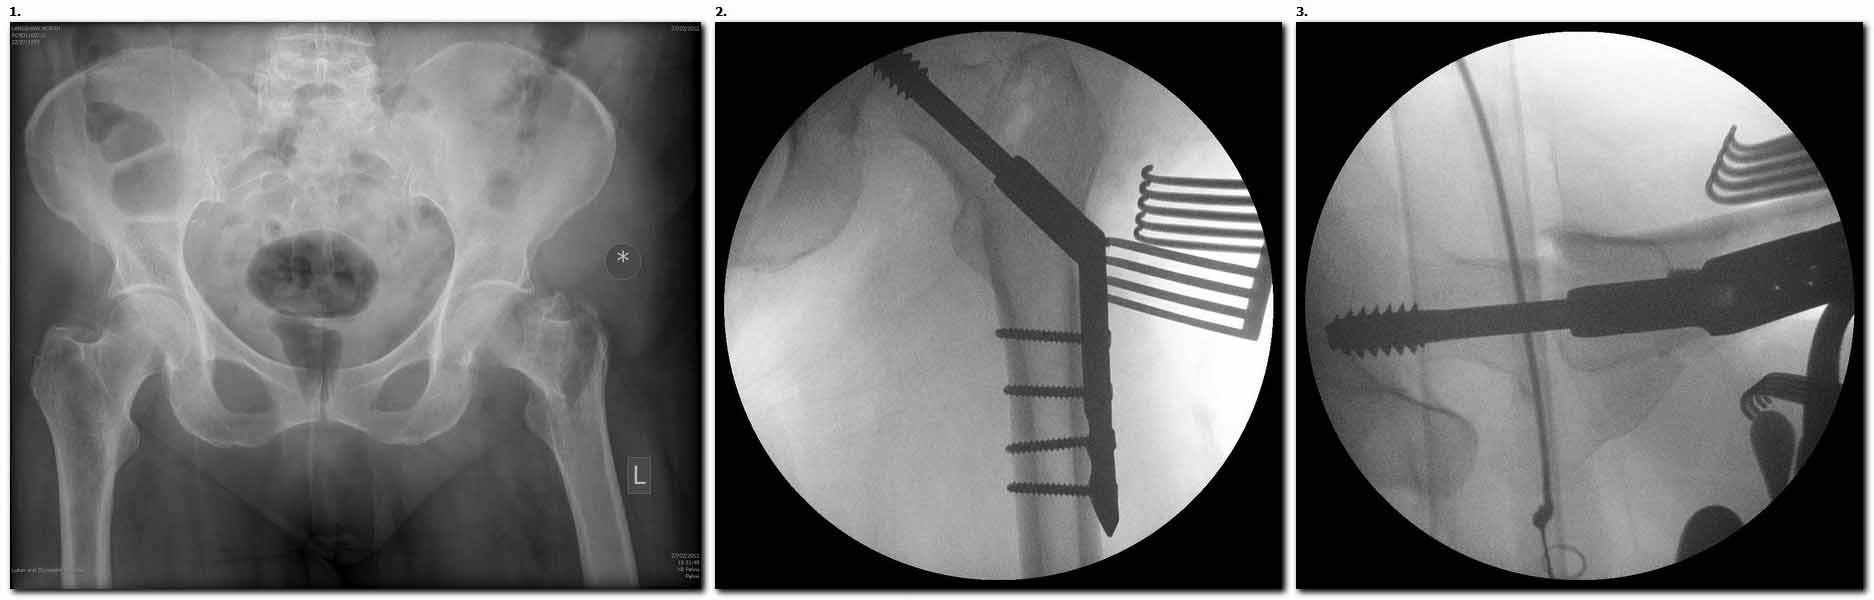

>  Банальный рутинный перелом чрезвертельной зоны лечимый DHS.

Не по теме, но все же спрошу. А почему выбран именно такой вариант

фиксации? Мы бы поставили цефаломедуллярный гвоздь (Gamma) и нагрузка сразу.

А по картинке можно сказать, что вроде бы все и неплохо. Предупредить

миграцию шеечного винта при наружной ротации диафиза во время ходьбы

достигают введением последнего поближе к переднему кортексу шейки. На Вашей

картинке винт "смотрит" кзади. Отсутствие дополнительной боковой опоры для

винта создает предпосылки для несостоятельности фиксации. (См. статью в

прикреплении). Поэтому с ранней активизацией пациента ,в данном случае, я

бы подождал.